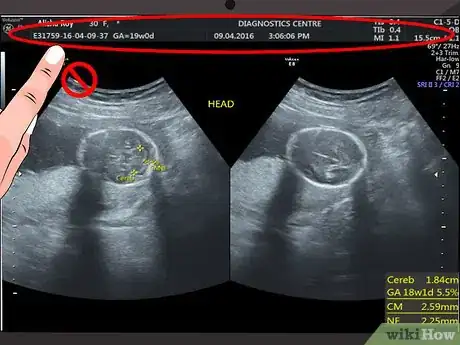

Disregard the text and numbers at the top of your scan. Most hospitals and ultrasound centers use this space to include details like your name, hospital reference number, or ultrasound machine settings. Since this information does not have anything to do with what you see on the ultrasound image, you can ignore this information.[1]

Identify your womb. You can identify the outline of your uterus by finding the white or light grey line around the edges of the ultrasound image. Just inside of this area, there should be a black area. This is the amniotic fluid.[6] [7]